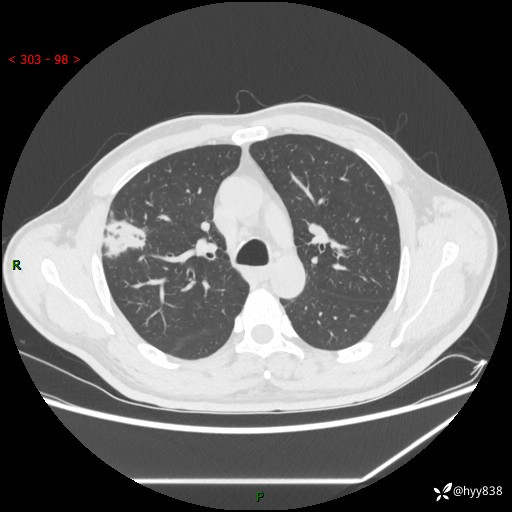

中年男性,体检发现肺占位2天。节段性实变,蜂窝样改变---结果公布~

现病史:患者2天前体检完善胸部CT提示:右上肺团块影,炎症可能,肿瘤性病变不除外,冠状动脉钙化,无咳嗽、咳痰,无寒战发热,无恶心、呕吐等其他特殊不适,未予以特殊治疗,现为明确病变性质来我院就诊,门诊以“肺肿物性质待查”收入我科。 起病以来,患者精神、饮食、睡眠可,大小便正常,体力体重较前无明显变化。

胸部CT平扫+增强